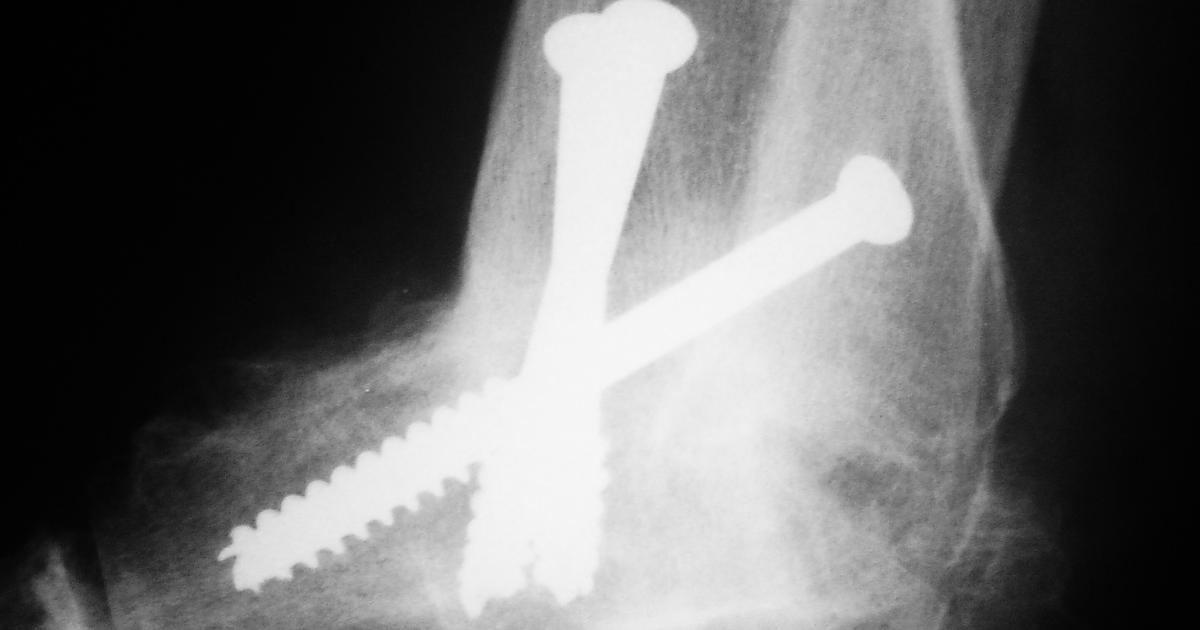

Arthrodesis

Arthrodesis, otherwise known as joint fusion surgery where the bones causing pain are welded together, is a procedure typically recommended for patients with severe arthritis pain caused by inflammation when a joint moves. Of course, this creates stiffness in the joint (ankylosis). Without the ability to move the joint, the pain typically subsides. In addition, the surgery can increase the stability of the patient's joint and allows them to place more weight on it. Joint fusion surgery is recommended when non-surgical arthritis treatments haven't provided relief. Other patients who may benefit from this procedure are those with back issues like scoliosis and degenerative disk disease. The surgery can be performed on the spine, feet, thumbs, fingers, wrists, or ankles. It's important to note there tends to be a long recovery period. In addition, it may not be the right option for individuals with certain health issues.